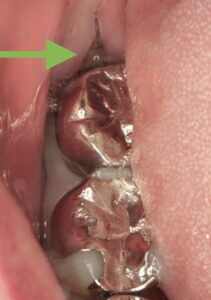

下の親知らずが横向きで生えている?埋まっている?

という状態です。

この矢印のところが虫歯になっているのです。

この歯は一度神経の治療をされているようですが、

隣の親知らずとの間が歯みがきできなかったせいで、虫歯がひろがり、大きな穴が空いています。

矢印の部分が親知らずが埋まっているところです。

この隣の銀歯の中で虫歯がひろがっているのです。